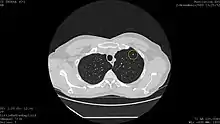

![]() Computed tomography (CT) scanner, the usually recommended screening technique | |

Results from large randomized studies have recently prompted a large number of professional organizations and governmental agencies in the U.S. to now recommend lung cancer screening in select populations. The 3 main types of lung cancer screening are low-dose, computerized tomographic (LDCT) screening, chest x-rays, and sputum cytology tests.[4] Currently multiple professional organizations, as well as the United States Preventive Services Task Force (USPSTF), the Centers for Medicare and Medicaid Services (CMS) and the European Commission's science advisors[5] concur and endorse low-dose, computerized tomographic screening for individuals at high-risk of lung cancer.